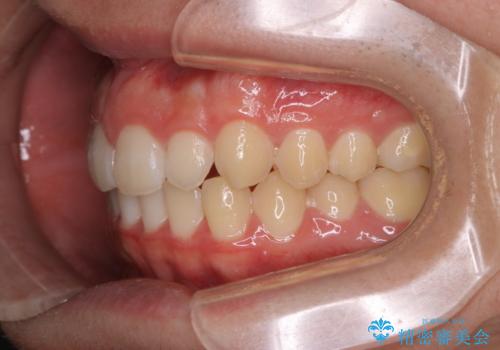

- 上の前歯が見えすぎて気になるとご相談にいらした方です。インビザラインにて前歯の圧下を行うことで歯の見え方の改善し、同時に奥歯の噛み合わせも改善を行いました。

インビザラインを正しく使用して頂けたおかげで、比較的難しいとされる歯の圧下も補助装置を使用せずに行うことが出来ました。上の前歯のラインが整ったことで笑った時の口元の印象を改善させることができ、大変喜んでいただけました。